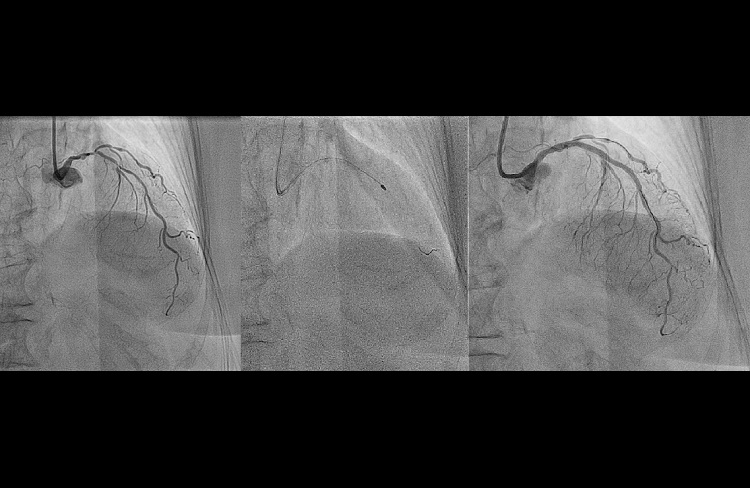

Pracownia Hemodynamiki/Radiologii Zabiegowej

OSTRY DYŻUR HEMODYNAMICZNY LECZENIE OSTRYCH ZESPOŁOW WIEŃCOWYCH I DYŻUR ZESPOŁU DS. LECZENIA OSTREJ ZATOROWOŚCI PŁUCNEJ: TELEFON CAŁODOBOWY 507 121 367

Pracownia powstała w 2012 roku po generalnym remoncie budynku Kliniki i została wyposażana w:

- nowoczesny sprzęt (cyfrowy system angiograficzny – Philips Healthcare Allura Xper Series FD20C;

- cyfrowy system do obrazowania wewnątrzwieńcowego IVUS Volcano Philips;

- systemy do oceny czynnościowej zwężeń w tętnicach wieńcowych i płucnych – FFR/iFR Volcano Philips, Acist RXi Bracco Iamging, Quantien Abott ) do zabiegów kardiologicznych oraz angiologicznych;

- system Rotablator – Rotational Angioplasty System, Boston Scientific;

- system do trombektomii reolitycznej AngioJet, Boston Scientific;

- system trombektomii aspiracyjnej – Penumbra Indigo).

Pracownia posiada akredytacje klasy B Polskiego Towarzystwa Kardiologicznego.

Dzięki wykwalifikowanemu personelowi jesteśmy liderami na skale europejską w leczeniu przezskórnym ostrej zatorowości płucnej (pracownia wyposażona jest w system do trombektomii reolitycznej AngioJet, Boston Scientific oraz trombektomii aspiracyjnej – Penumbra Indigo) oraz przewlekłego zakrzepowo-zatorowego nadciśnienia płucnego (CTEPH).

Pracownia wykonuje szeroką gamę zabiegów diagnostycznych i leczniczych w obrębie łożyska płucnego, krążenia wieńcowego oraz wad strukturalnych serca. W pracowni wykonywane są zabiegi zarówno w trybie ostrodyżurowym (w ramach 24 godzinnego ostrego dyżuru hemodynamicznego) oraz kompleksowe zabiegi w trybie planowym. Specjalizujemy się w nowoczesnych dostępach naczyniowych u chorych poddawanych koronarografii (dystalny dostęp od tętnicy promieniowej oraz łokciowej) co skutkuje znikomą liczbą powikłań oraz krótkim pobytem w oddziale szpitalnym. U pacjentów z silnie uwapnionymi zwężeniami w tętnicach wieńcowych, u których klasyczna przezskórna angioplastyka jest nieskuteczna wykonujemy z powodzeniem rotablację (zabieg wykonywany z zastosowaniem wysokoobrotowego wiertła diamentowego modyfikującego blaszkę miażdżycową, rocznie > 25 zabiegów co plasuje nasz ośrodek w gronie liderów tej metody w Polsce- system Rotablator – Rotational Angioplasty System, Boston Scientific). Dzięki współpracy z Kliniką Medycyny Transplantacyjnej, Nefrologii i Chorób Wewnętrznych skutecznie i bezpiecznie leczymy inwazyjnie chorych z zaawansowanymi postaciami niewydolności nerek.

Zabiegi związane z diagnostyką i leczeniem stabilnej choroby wieńcowej oraz ostrych zespołów wieńcowych:

- diagnostyka inwazyjna choroby wieńcowej oraz ostrych zespołów wieńcowych (koronarografia);

- zabiegi przezskórnej angioplastyki wieńcowej (PTCA) w świeżym zawale serca oraz stabilnej chorobie wieńcowej;

- zabiegi rotablacji wieńcowej w uwapnionych blaszkach miażdżycowych;

- diagnostykę zmian granicznych stwierdzonych w trakcie koronarografii (zwężenia 40-70%), przy pomocy oceny czynnościowej zwężeń (FFR) oraz oceny morfologicznej (ultrasonografii wewnątrzwieńcowej -IVUS);

- zarówno zabiegi diagnostyczne, jaki i terapeutyczne wykonywane są w większości z dostępu od tętnicy promieniowej, rzadziej od tętnicy ramiennej i w niewielkim odsetku od pachwiny (tętnicy udowej, < 3%).